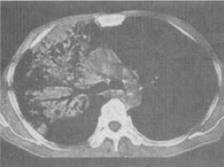

患者男,28岁,咯血伴盗汗1个月,CT如图,最可能的诊断为()。

A、干酪性肺炎

B、大叶性肺炎

C、过敏性肺炎

D、肺不张

E、肺泡细胞癌

A